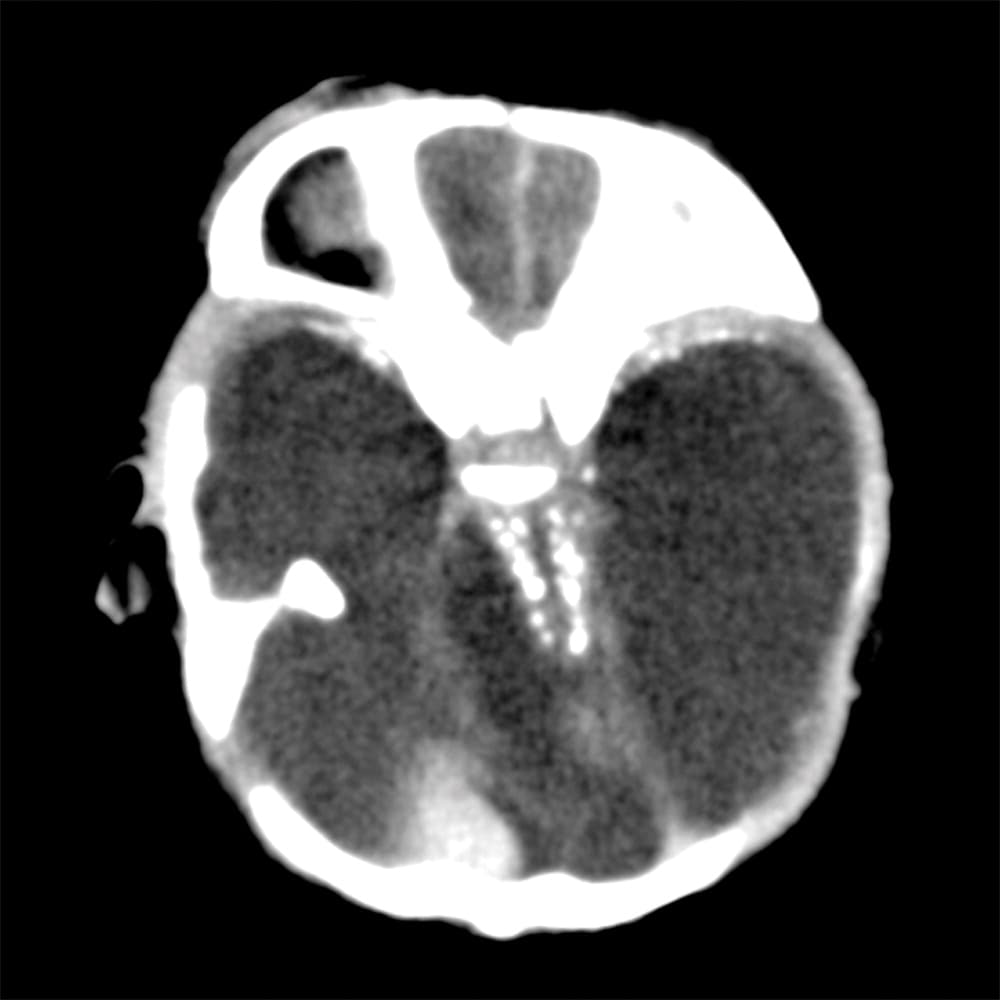

Investigadores brasileños difundieron este martes el mayor número hasta ahora disponible de imágenes computarizadas, resonancias magnéticas y ultrasonidos, de bebés y fetos infectados con el virus del Zika. El daño es mucho mayor del que anticipaban.

Así describe la radióloga brasileña Fernanda Tovar-Moll lo que vio al analizar centenares de imágenes computarizadas, resonancias magnéticas y ultrasonidos de 45 bebés que se contagiaron de zika en el vientre materno en el estado de Paraíba, en el noreste del país, donde el brote ha sido severo.

La mayoría nació con microcefalia, cuya característica más llamativa es que tienen el cerebro y la cabeza más pequeña. Pero muchos sufren una escala y severidad de daño mucho peor en partes importantes del cerebro como el cuerpo calloso, que conecta los dos hemisferios; el cerebelo, que juega un papel significativo en el movimiento, equilibrio y habla; y los ganglios basales, que controlan el pensamiento y la emoción.

Tovar-Moll es coautora de un estudio publicado el martes en la revista Radiology y fue liderado por la doctora Patricia Soares de Oliveira-Szejnfeld, a quien se le da crédito por establecer el vínculo entre el zika y la microcefalia en Brasil.